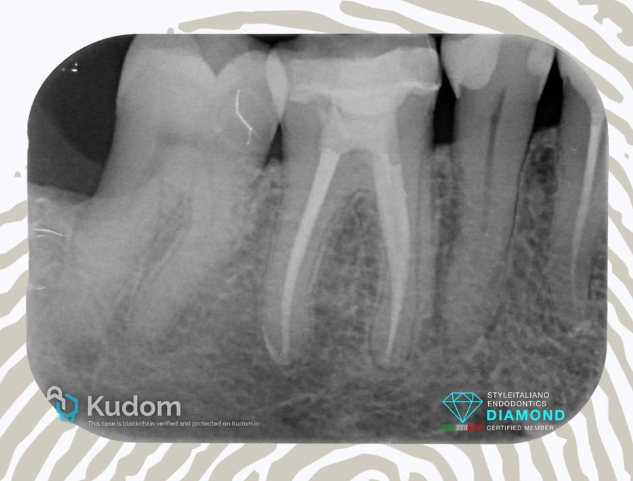

3.5: Retreatment - Lesion - Big Foramen - CHC & CeraSeal - 5 years recall

Patient was refereed for the retreatment of a symptomatic 3.5 with periapical lesion.

After the complete desobturation the canal was shaped and deeply cleaned and the canal was dressed with Calcium Hydroxide.

After 2 weeks the canal was obturated using CeraSeal bioceramic sealer with the Cold Hydraulic Condensation technique.

Thanks to a good cone fit the overfilling was well controlled at foramen level, but it’s impossible control the overfilling from lateral canal, as a lateral lesions is always concentric to the P.O.E. of a lateral canal.

The recall at 5 years shows a stable and complete healing of the lesion, no sealer resorption…….it’s all about outcome!!!!